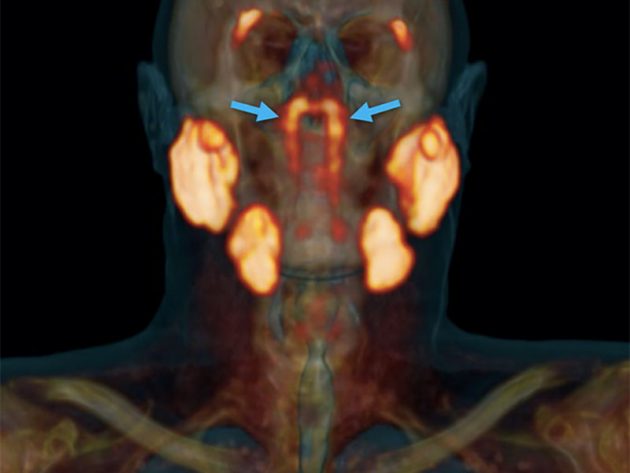

Wie Mediziner um Onkologen Wouter Vogel und Matthijs Valstar vom Netherlands Cancer Institute aktuell im Fachjournal “Radiotherapy & Oncology” (DOI: 10.1016/j.radonc.2020.09.034) berichten, handelt es sich um zwei bislang unbekannte Speicheldrüsen. Entdeckt wurden diese hinter dem Nasenrachen (Nasopharynx) während einer Studie mit einer neuen Scan-Methode zur Erkennung und Untersuchung von Krebs im Nacken- Kopf-, Rachen- und Zungenbereich. Tatsächlich seien die Strukturen erst jetzt und nur mit Hilfe der neuen PSMA-PET/CT-Technologie zu finden und darstellbar.

„Bislang waren drei große Speicheldrüsen bekannt (Ohr-, Unterkiefer- und Unterzungespeicheldrüse) bekannt. Im Nasenrachen sollten nach bisherigem medizinischem Wissen, eigentlich keine weiteren großen Speichedrüsen sein, waren dort bislang doch nur kleine Speicheldrüsen bekannt“, erläutert Vogel und erinnert sich weiter: „Sie können sich vielleicht unser eigenes Erstaunen vorstellen, also wir diese zusätzlichen großen Speicheldrüsen auf den Scans sahen (s. Abb. o.).“

Nach ihrer ersten Entdeckung untersuchten die Mediziner gemeinsam mit Kollegen der Universität Utrecht 100 weitere Personen – und fanden bei allen die bislang unbekannten großen Speicheldrüsen im Nasenrachen, die die Wissenschaftler nun aufgrund der anatomischen Position der Drüsen als „tubarial glands“ (Rachenspeicheldrüsen?). Die Existenz der Drüsen konnte dann auch direkt durch Autopsien bestätigt werden.